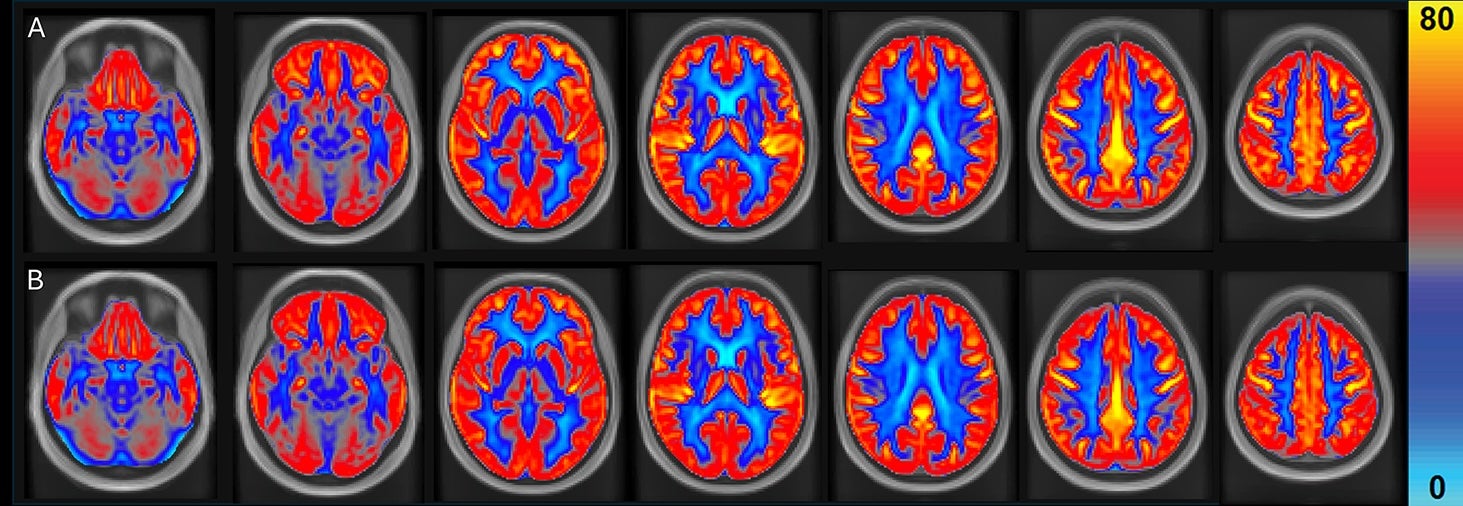

Average cerebral blood flow is shown to increase, in yellow, after eating peanuts in brain scans listed as A. The scans in B mark control periodsopen image in galleryAverage cerebral blood flow is shown to increase, in yellow, after eating peanuts in brain scans listed as A. The scans in B mark control periods (Dr. Peter Joris)

“However, in contrast to our two earlier studies that reported only regional changes in cerebral blood flow, the current findings also demonstrate increases in global cerebral blood flow and gray matter cerebral blood flow of 3.6 percent and 4.5 percent, respectively,” Joris and his team wrote with the current findings.

“To illustrate the relevance of this finding, global cerebral blood flow decreases with 0.37 percent per year as we age.”